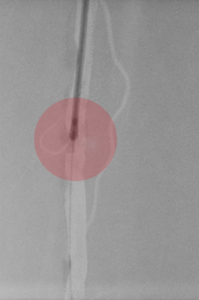

6. Fibrinolyse – medikamentöses Auflösen von Blutgerinnseln

Gefäßverschließende Blutgerinnsel können auch durch Medikamente aufgelöst werden, um den Blutfluss wiederherzustellen. Damit dieses Medikament sicher und effektiv wirken kann, wird es über einen Katheter direkt zum Verschluss gebracht. Das erfolgt über eine langsame mehrstündige Gabe. Zur Verbesserung der Wirkung kann durch Spezialkatheter das Medikament mit Hilfe von Schallwellen in das Blutgerinnsel transportiert werden.